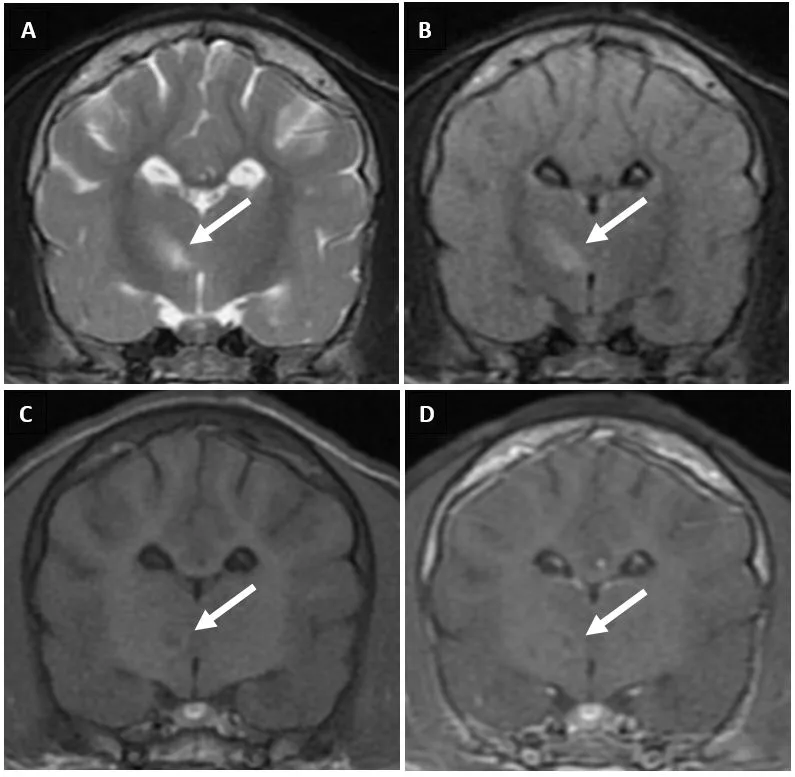

Pending CDV results, brain MRI and CSF analysis were performed to evaluate for other structural causes of seizures. Brain MRI showed multifocal, asymmetric, intra-axial lesions in the left cerebrum and brainstem (Figure 1). Most likely differential diagnoses included infectious encephalopathies (eg, CDV infection) or meningoencephalitis of unknown etiology. CSF analysis was normal, and CSF distemper titer was negative (<1:4). Results likely reflected the acute stage of CDV encephalitis, during which CNS lesions are primarily characterized by direct viral replication and cellular injury leading to noninflammatory demyelinating lesions.1-3

Brain MRI of Poncho, on which a hyperintense, intra-axial lesion in the right thalamus can be seen on T2-weighted (A, arrow) and fluid-attenuated inversion recovery (B, arrow) axial images. The lesion is hypointense on the T1-weighted axial image (C, arrow). Findings suggest high fluid content common with inflammatory lesions. Postcontrast T1-weighted axial image following administration of gadolinium IV showed no contrast (D, arrow).

Thoracic radiographs may show an interstitial to alveolar lung pattern suggestive of bronchopneumonia.1 MRI often shows multifocal, intra-axial lesions supportive but nonspecific for CDV encephalitis, as they can be consistent with other infectious or inflammatory diseases.1,6,10